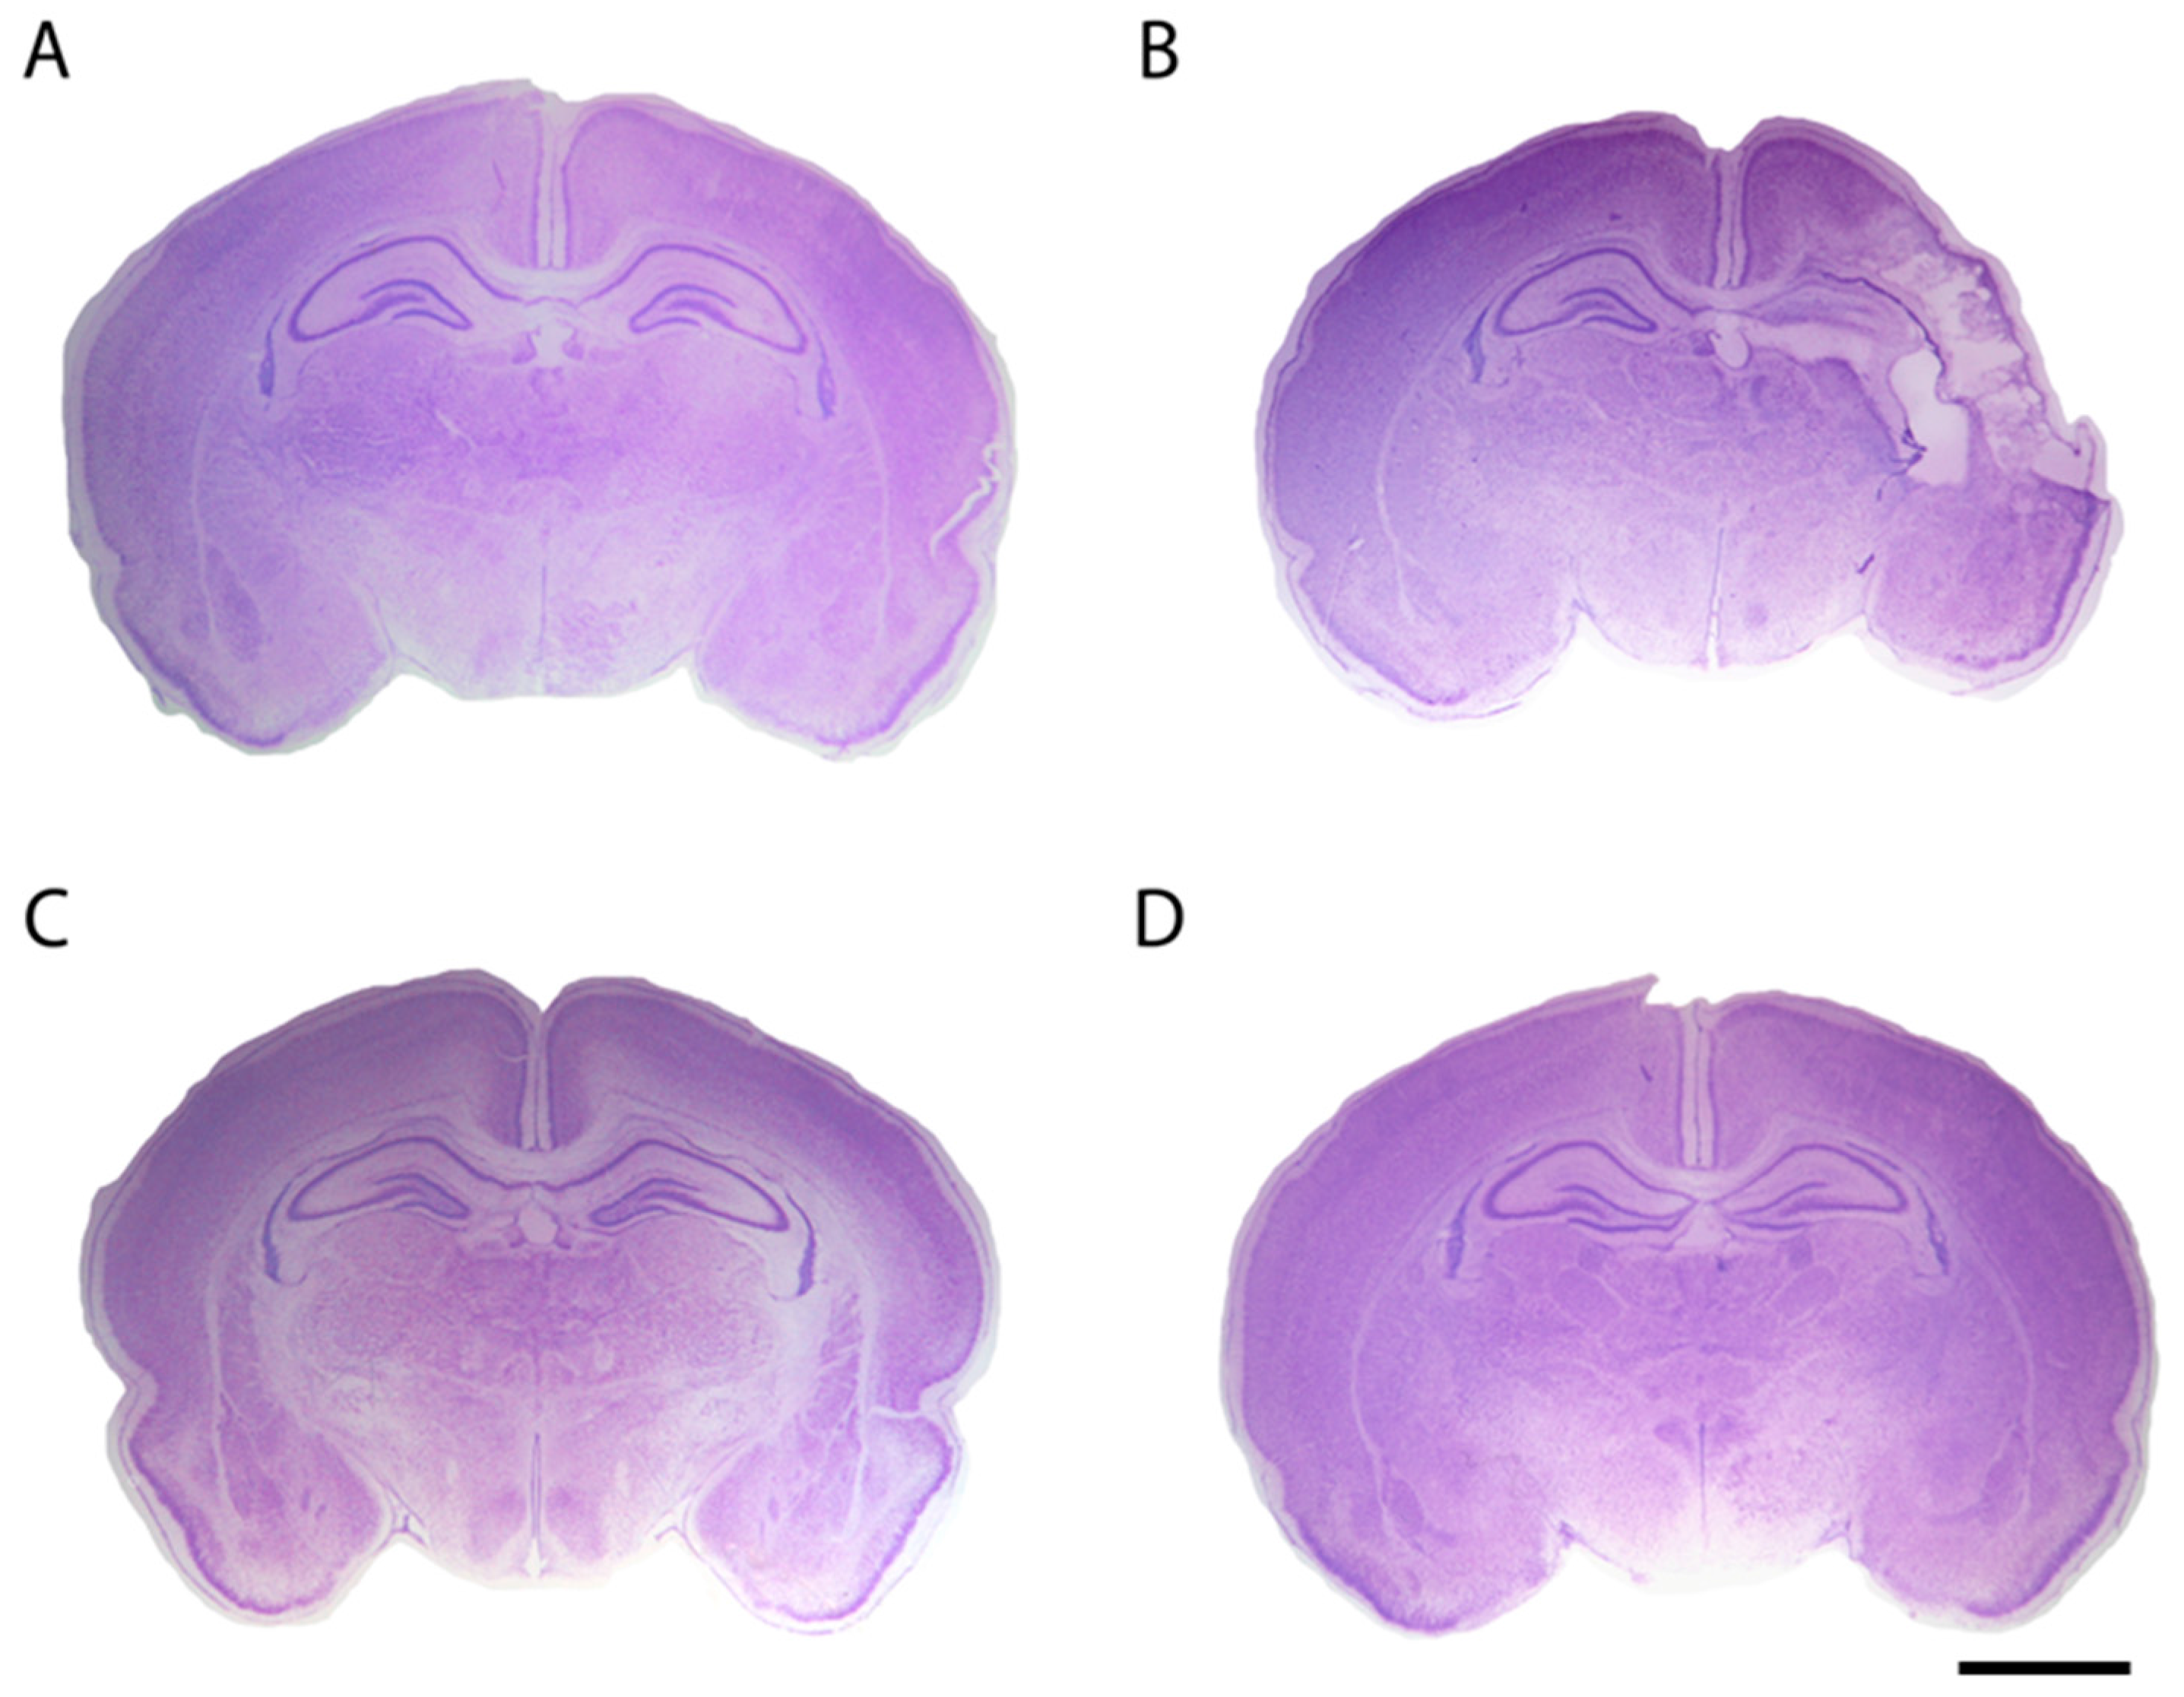

Resveratrol, when administered before the HI event, was found to be a potent protective agent that diminished tissue loss (Figure 3) and consequently infarct area both in rats and mice [86,87,88]. It also preserved myelination and minimized the astroglial reactive response [86,87]. Additionally, its neuroprotective effects were found to be long lasting because it was able to improve long-lasting cognitive deficits induced by hypoxia–ischemia [86,87]. Both non-spatial and spatial working memories, assessed by different behavioral tests, were found to be significantly improved in resveratrol-treated neonatal rodents [86,87,88], and these findings might be associated with the preservation of gray and white matter, especially at the level of the cortex and the hippocampus. The beneficial effects of resveratrol to recover the alteration of auditory-evoked potentials and reduce morphological damage in the inferior colliculus after rat perinatal asphyxia have also been reported [89]. Perhaps one of the best known mechanisms of action of resveratrol is that of apoptosis prevention. West et al. [88] reported that caspase-3 activation is minimized by resveratrol. Likewise, it has also been proposed that one of the mechanisms for this neuroprotection may be related to the maintenance of the mitochondrial state, by protecting the integrity of the inner membrane and the transmembrane potential, and by decreasing ROS production [86,89].

Figure 3.

Representative stereomicroscopic photographs of rat brain sections (interaural distance 5.40 mm and bregma −3.60 mm) stained with Nissl at P14 from different experimental groups: (A) the control group; (B) in the hypoxia–ischemia (HI) group, pups underwent permanent left common carotid artery occlusion and, after two hours of recovery, they were asphyxiated for 135 min in 8% O2; (C) the HI group pretreated with resveratrol (20 mg/kg), which was intraperitoneally administered 10 min before hypoxia [86]; and (D) the HI group pretreated with docosahexaenoic acid (1 mg/kg) injected intraperitoneally 10 min before hypoxia [90]. The brain from the HI group presented an evident loss of tissue in the ipsilateral side, while brains pretreated with either resveratrol or docosahexaenoic acid were similar to the control brain, without obvious histological signs of infarct. Scale bar: 2.5 mm.